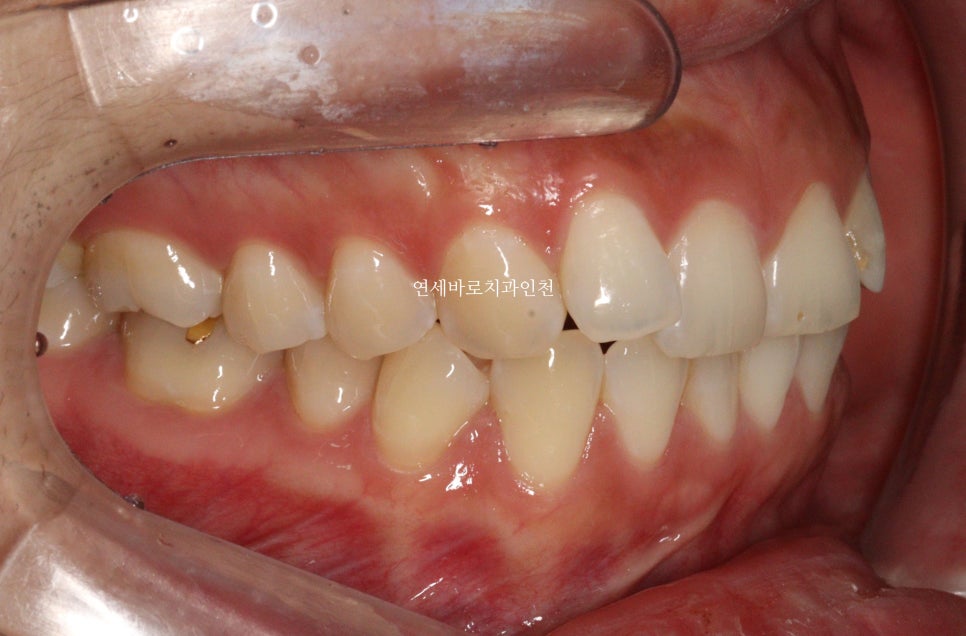

치열이 삐뚤삐뚤하신 상태입니다.

치열의 배열 및 골격적인 분석 결과 무턱과 입술이 자연스럽게 다물어 지지 않는 것도 발견되었습니다.

위 사진은 어느정도 힘을 주고 찍은 사진입니다.

치아의 배열만 진행한다면 조금 더 간단하게 진행할 수 있을지 모르지만,

환자분과의 충분한 상담 후 무턱도 함께 개선하기로 했습니다.